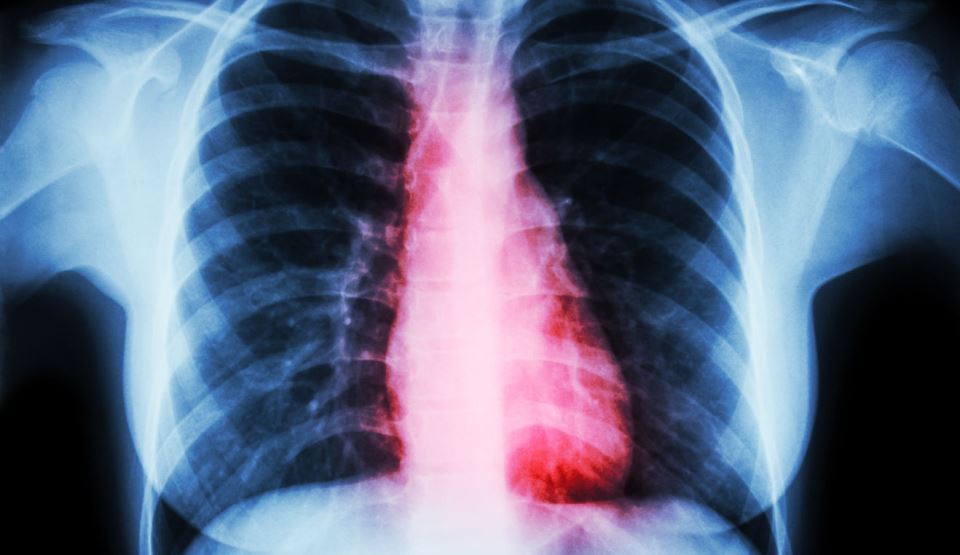

Consumul regulat de ardei iuţi poate reduce riscul de infarct sau atac cerebral

Un nou studiu desfăşurat în Italia a demonstrat că persoanele care consumă în mod regulat ardei iute prezintă un risc redus de boli de inimă şi accident cerebral, relatează CNN, citat de Mediafax.

Studiul a fost făcut pe 23.000 de persoane, ale căror obiceiuri alimentare au fost monitorizate pe o periodă de 8 ani.

Cercetătorii au descoperit că persoanele care au consumat ardei iute de cel puţin 4 ori pe săptămână prezentau un risc cu 40% mai mic de a dezvolta boli de inima sau accident cerebral.

„Ceea ce am observat este că indiferent de tipul de alimentaţie, una mediteraneană sau una mai puţin sănătoasă, consumul de ardei iute a avut aceleaşi efecte benefice”, a declarat Marialaura Bonaccio, autoarea studiului.